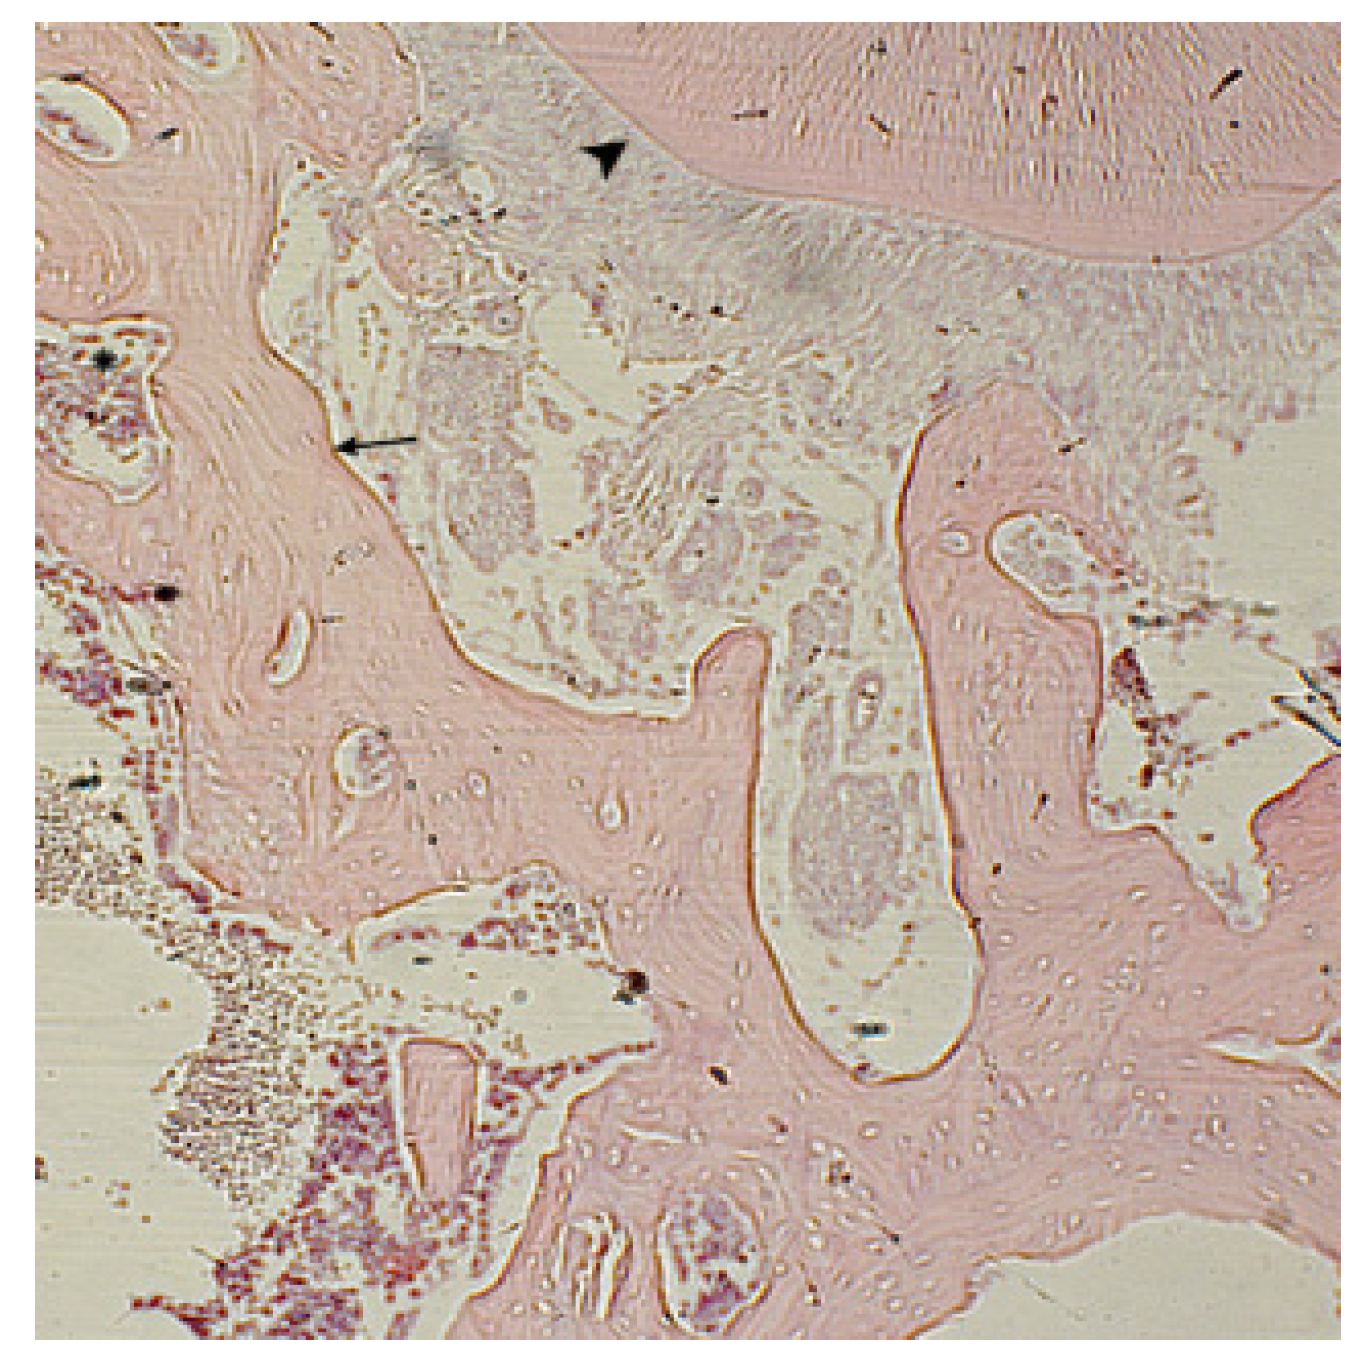

) are recorded. Hematoxylin-eosin staining. Magnification x250.

). Hematoxylin-eosin staining. Magnification x400.

) are detected, in the bone tissue “isolated” osteocytes (^). Hematoxylin-eosin staining. Magnification x480.